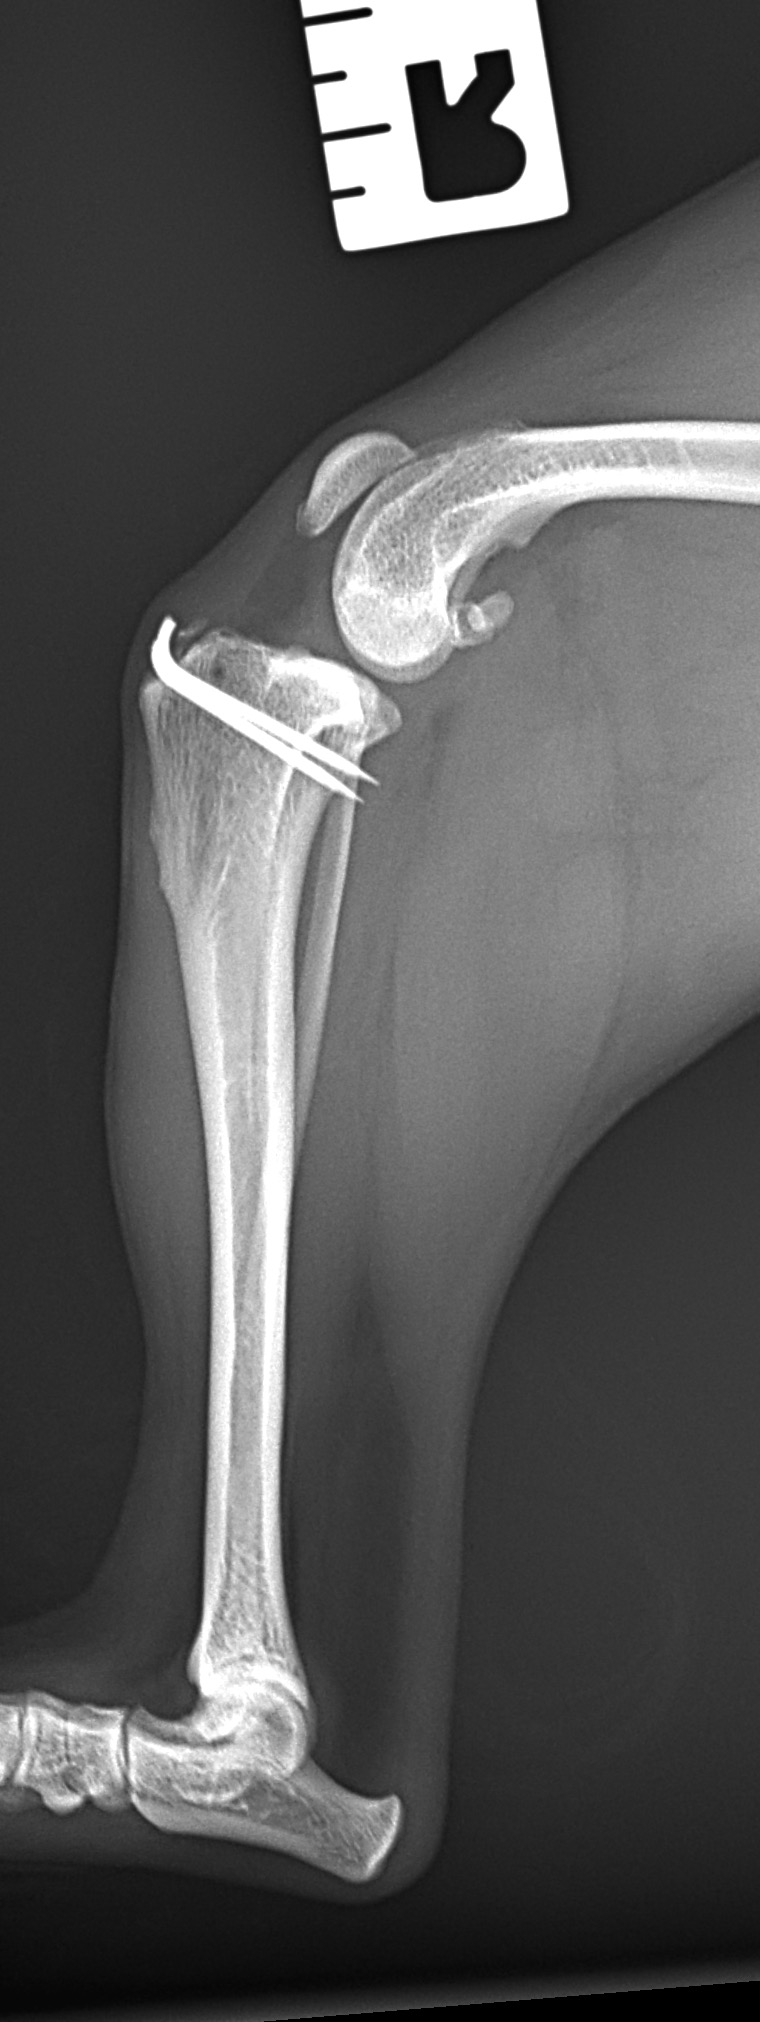

前十字靭帯部分断裂に対するLSS(ラテラルスーチャー法)

小型犬の前十字靭帯部分断裂にラテラルスーチャー法(以下LSS)を実施した。以前、膝蓋骨内方脱臼により大腿骨滑車造溝術、脛骨粗面移行術を行っている。今回、後肢に違和感があるとのことで早急に来院された。幸い完全断裂ではなく部分断裂のようである。大腿骨遠位にチタン製スパイクワッシャー とスクリューによりアンカーを作成、脛骨近位にボーンホールを形成し人工靭帯で締結した。小型犬では症状、年齢、ライフスタイルなどに合わせてLSSによる膝関節安定化術も治療オプションの一つである。